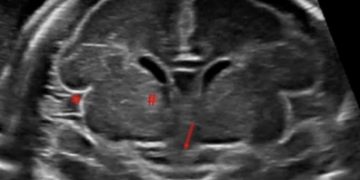

Leggi di piùCari soci, questo mese un nuovo video "How to do", sull'approccio avanzato all'encefalo fetale, ovvero sulla Neurosonografia. Grazie ad Andrea Dall'Asta! Il video è accessibile ai soli soci SIEOG attraverso...

Leggi di piùCari soci, questo mese un nuovo video "How to do", sull'approccio base allo studio della fossa cranica posteriore. Grazie a Daniele Di Mascio! Il video è accessibile ai soli soci...